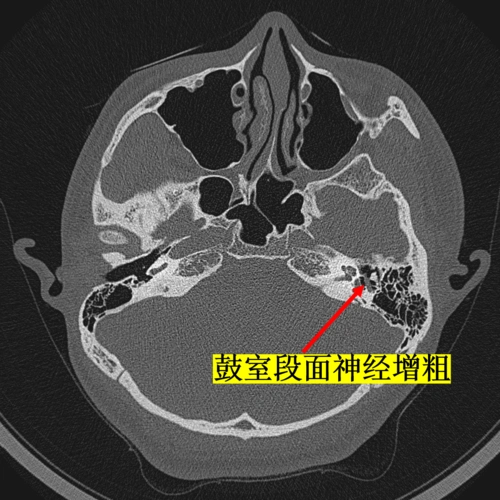

面神经瘤的影像学特点